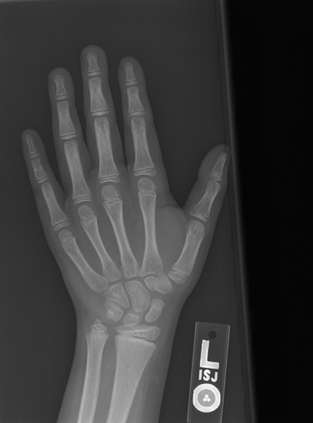

Deep neural networks are increasingly being used for the analysis of medical images. However, most works neglect the uncertainty in the model's prediction. We propose an uncertainty-aware deep kernel learning model which permits the estimation of the uncertainty in the prediction by a pipeline of a Convolutional Neural Network and a sparse Gaussian Process. Furthermore, we adapt different pre-training methods to investigate their impacts on the proposed model. We apply our approach to Bone Age Prediction and Lesion Localization. In most cases, the proposed model shows better performance compared to common architectures. More importantly, our model expresses systematically higher confidence in more accurate predictions and less confidence in less accurate ones. Our model can also be used to detect challenging and controversial test samples. Compared to related methods such as Monte-Carlo Dropout, our approach derives the uncertainty information in a purely analytical fashion and is thus computationally more efficient.